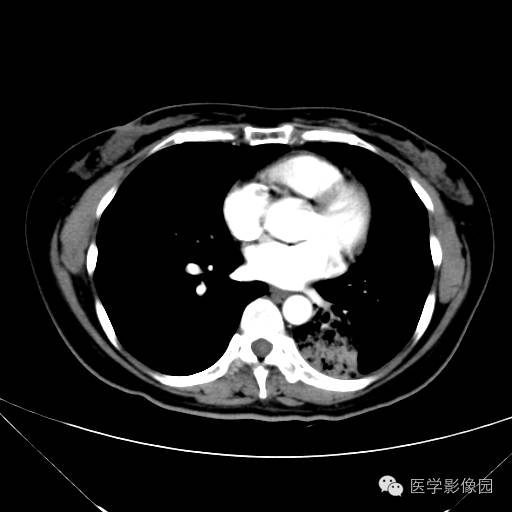

肺叶实变性支气管肺泡癌1例CT影像表现